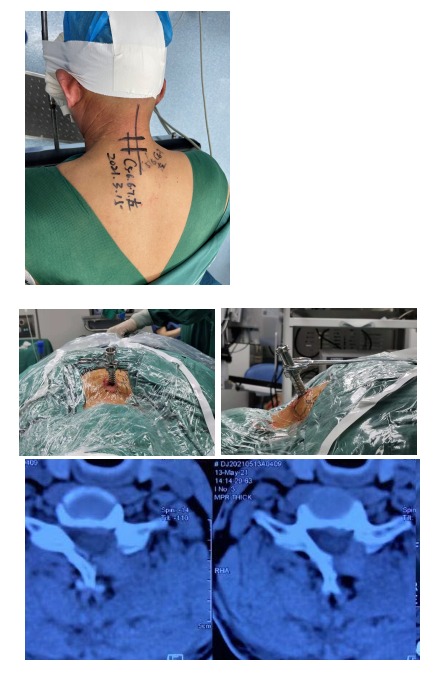

病例展示

主诉:四肢无力伴行走不稳5年

现病史:患者5年前无明显诱因出现四肢无力,伴行走不稳,似“踩棉花感”,以左侧为重,无头晕等症状,未系统检查治疗;近来自觉症状逐渐加重,行走困难,在当地医院行颈椎MRI检查提示:C3-4、C5-6、C6-7平面椎管狭窄,颈脊髓受压明显,在外院就诊给予针灸、理疗、药物等综合保守治疗,效果欠佳。今日为求进一步诊治,来我院就诊,遂以脊髓型颈椎病为诊断收住我科。发病以来,神志清楚,精神尚可,饮食正常,睡眠一般,体力正常,大小便正常。

专科检查:颈椎生理曲度变直,颈椎C5-C7棘间及双侧棘突旁压痛,左手食指、中指感觉麻木,左侧肱三头肌肌力III级,左手握力III级,右侧肱三头肌肌力IV级,右侧握力IV级,双下肢肌力IV级,左侧Hoffmann征(+),双上肢桡骨膜反射(++++)、肱二头肌腱反射(++++)、肱三头肌腱反射(++++),双下肢膝腱反射(++++),踝阵挛(—),Babinski征(+)。

影像资料